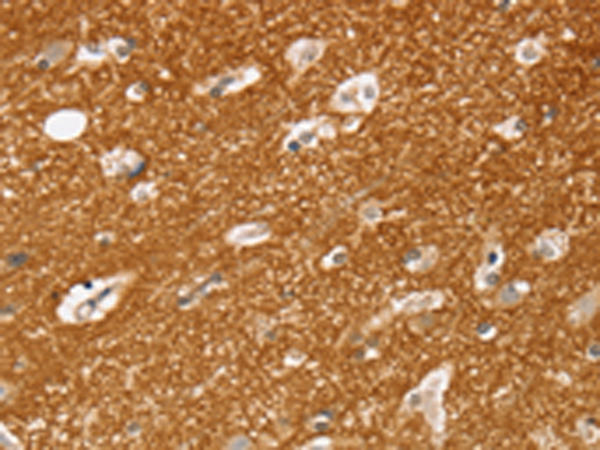

分类: 科研抗体货号: P08752别名: SEMAF; SEMAI; SEMACL1; M-SEMA-F应用: IHC反应种属: Human, Mouse